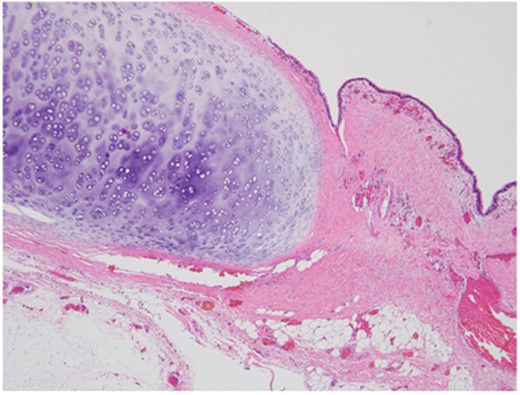

Microscopic view of resected bronchogenic cyst showing ciliated epithelium and cartilage (H&E stain, ×20).